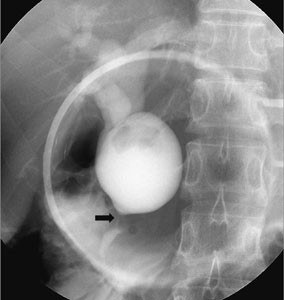

Fig. 1